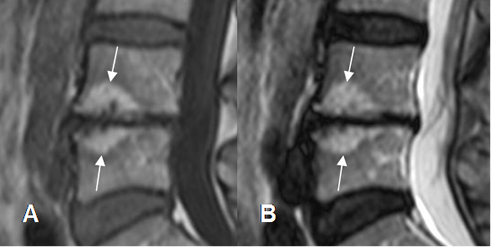

Fig 117. Cambios degenerativos Modic tipo II.

A: RM sagital en T1 y B: RM sagital en T2. Cambios degenerativos en las placas terminales, hiperintensos en ambas secuencias.